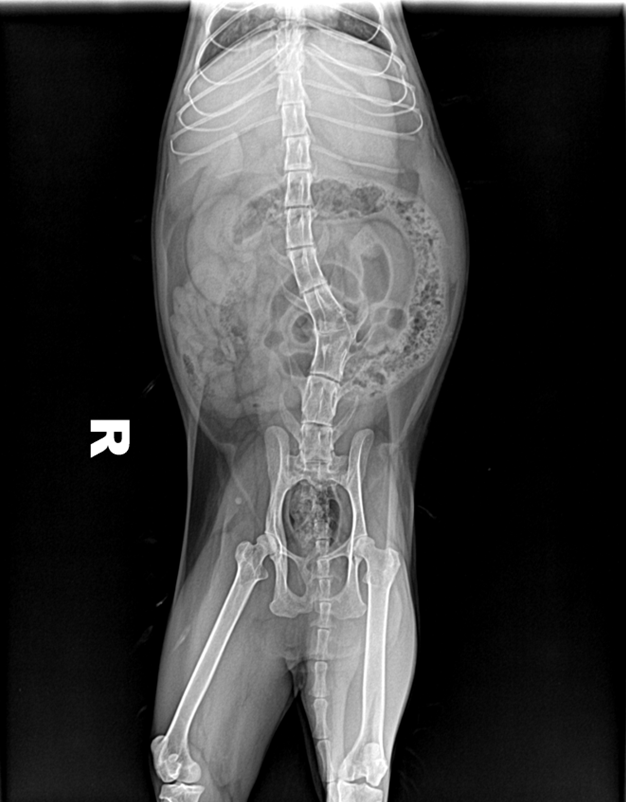

(2)识别X线影像中的颈椎、胸椎、腰椎和荐椎,并能确定属于位置(图6-12、图6-13)。

(3)识别椎间隙、椎间孔、棘突、横突的X线影像(图6-12、6-13)。

犬、猫正常脊柱由7节颈椎、13节胸椎、7节腰椎、3节荐椎和数量不定的尾椎连接而成。各椎骨间有椎间盘,但第1~2颈椎关节、3节荐椎之间无椎间盘。椎间盘由髓核和纤维环组成,呈软组织阴影,在X线片上表现为低密度的裂隙。邻近的椎间隙大致相等,但正常的第10~11腰椎椎间隙较狭窄。

犬椎体侧位投照显示似方形,多数脊椎可显示椎弓、椎管的背侧缘与腹侧缘、椎体前后端骨骺、棘突、横突和椎体。猫的椎体较长,侧位显示似长方形,椎弓根、关节突欠清楚,椎间孔背侧缘不如犬易见。棘突在腹背位投照时呈致密狭长的断面高密度阴影。侧位投照时,相连椎骨的大小、形状和密度大致相同。第2颈椎棘突靠近第1颈椎椎弓,或与之重叠。第6颈椎横突宽大,呈翼状。胸椎椎体长度略比颈椎椎体短。第11胸椎棘突垂直向上,称为直椎。直椎之前的胸椎棘突斜向后上方,而直椎以后的胸腰椎棘突则斜向前上方。后段4~5节胸椎的的关节后突下方、椎间孔的前上界处,可显示一细小、类三角形的副突阴影。